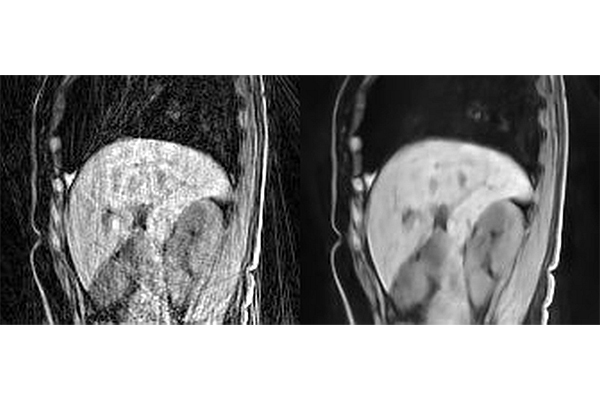

Example images reconstructed using (A) regridding or (B) the Phase2Phase method developed by Hongyu An and Ulugbek Kamilov. The Phase2Phase image was obtained by directly applying the Phase2Phase network trained on CAPTURE images to image in (A).

When patients undergo an MRI, they are told to lie still because even the slightest movement compromises the quality of the images and can create blurred spots and speckles known as artifacts. Moreover, a long acquisition time is usually required to provide high-quality MRI images. A team of researchers from Washington University in St. Louis has found a new deep-learning method that can minimize artifacts and other noise in MRI images that come from movement and a short image-acquisition time.

Two radiologists, who were blinded to which reconstruction method was used on the images, reviewed the images for their sharpness, contrast and artifacts. They found that the Phase2Phase and UNet3DPhase images had higher contrast and fewer artifacts than the compressed sensing images. The UNet3DPhase and Phase2Phase images were reported to be sharper than the compressed sensing images by one reviewer, but not by the other. The Phase2Phase and UNet3DPhase images were similar in sharpness and contrast, while the UNet3DPhase images had fewer artifacts. The Phase2Phase images preserve the motion vector fields, while the compressed sensing images artificially reduced the motion vector fields.